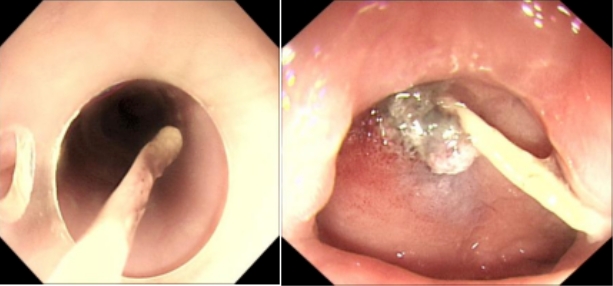

在多學(xué)科專家的共同努力下,醫(yī)生們與患者及家屬充分溝通,詳細(xì)交代了麻醉及內(nèi)鏡治療的風(fēng)險(xiǎn)與利弊。在取得患者及家屬的同意后,梁小波主任帶領(lǐng)團(tuán)隊(duì)再次為患者進(jìn)行無(wú)痛胃鏡檢查及內(nèi)鏡下治療。緊張的操作過(guò)程中,內(nèi)鏡中心李學(xué)志醫(yī)生憑借精湛的技術(shù),小心翼翼地循腔進(jìn)鏡到達(dá)十二指腸,那根隱藏在患者體內(nèi)的“罪魁禍?zhǔn)住苯K于被成功取出——竟是一根長(zhǎng)達(dá)2.5cm的魚(yú)刺!隨后,醫(yī)生們又順利完成了十二指腸球部創(chuàng)面的止血工作,經(jīng)檢查創(chuàng)面無(wú)滲血,手術(shù)取得了圓滿成功。

△異物取出圖片